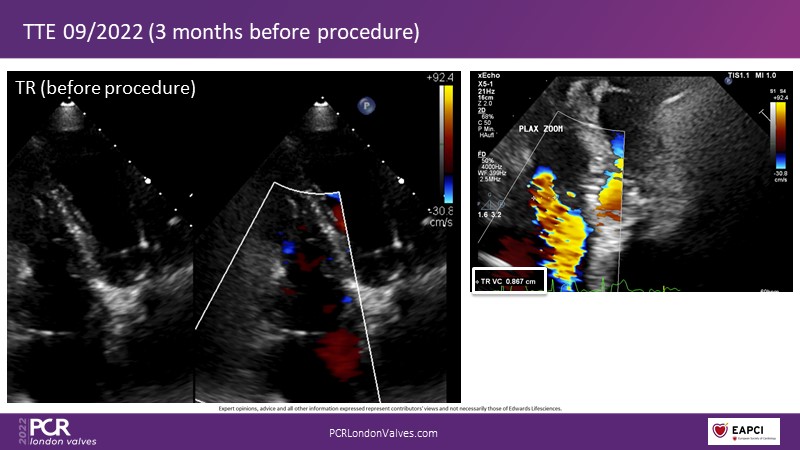

This innovative session takes you through the patient selection and anatomical characteristics when selecting amongst the different transcatheter options to treat tricuspid regurgitation, followed by a recorded demonstration using the PASCAL Precision repair system.

- To discuss the anatomical considerations that define suitable candidates for the different portfolio of options to treat tricuspid regurgitation

- To review different transcatheter options to treat tricuspid regurgitation and their key differentiators